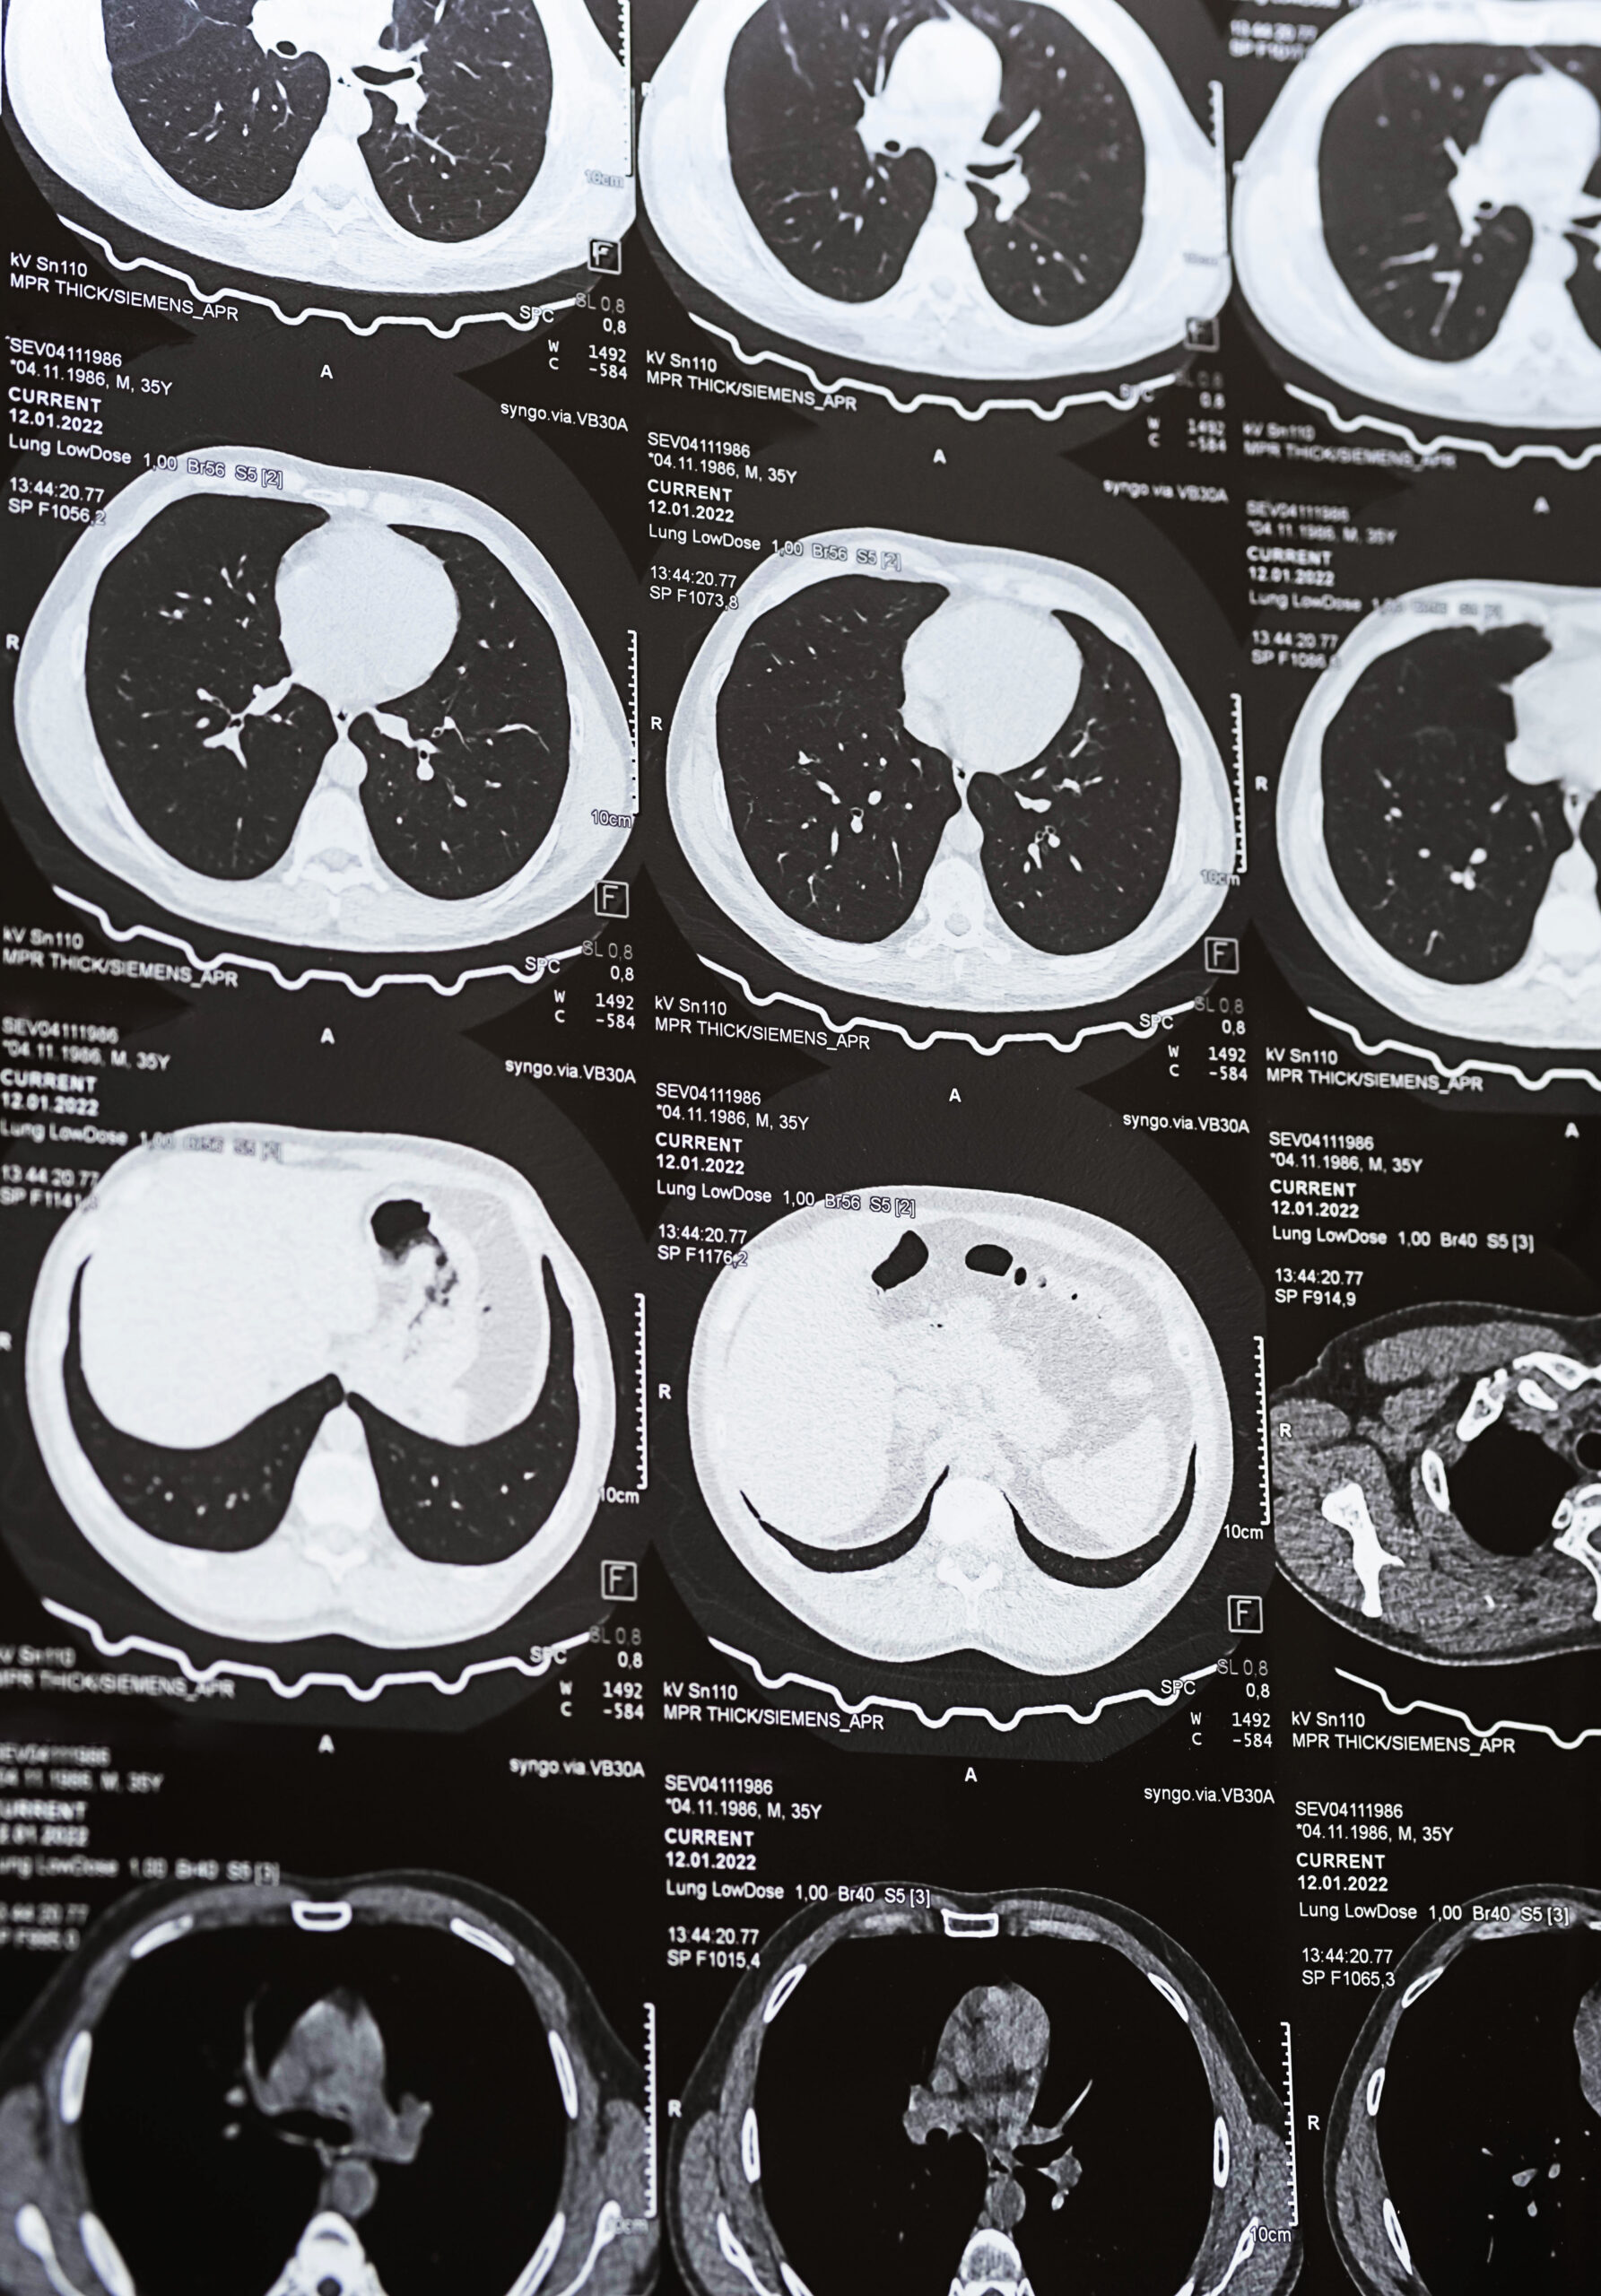

A CT lung screening uses low-dose computed tomography to produce detailed, three-dimensional images of the lungs. The scan is non-invasive, does not require a contrast injection, and is completed in just a few minutes. This approach allows us to evaluate and examine lung tissue carefully while keeping radiation exposure to a minimum.

A board-certified radiologist carefully reviews the images, assessing lung tissue for nodules, structural changes, or other findings relevant to screening criteria.